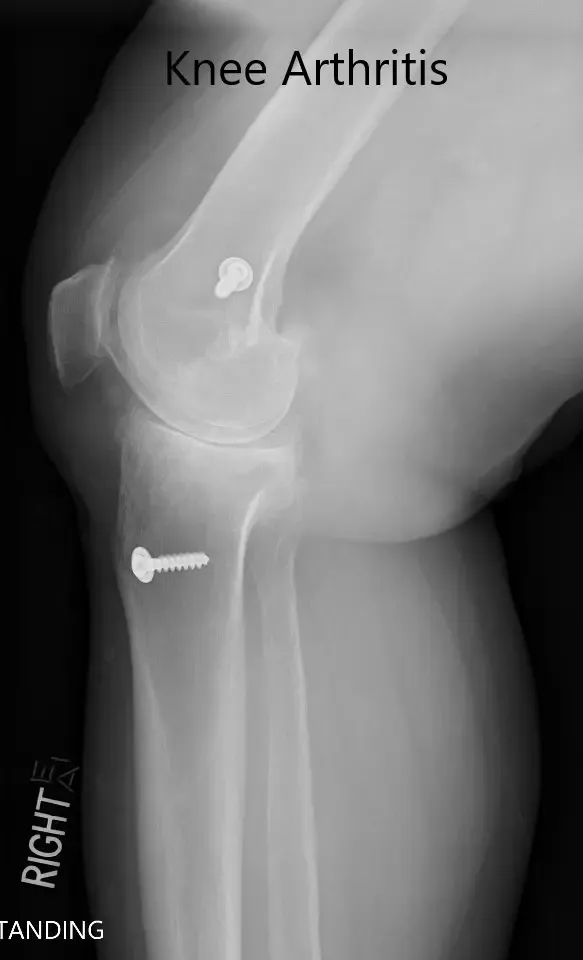

Radiografía preoperatoria que muestra las vistas AP y laterales de la rodilla derecha con tornillos retenidos, consistentes con la reconstrucción del LCA.

Radiografía preoperatoria que muestra las vistas AP y laterales de la rodilla derecha con tornillos retenidos, consistentes con la reconstrucción del LCA (imagen 3)